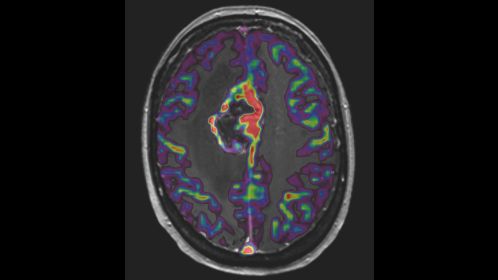

*pCASL (pseudo-Continuous Arterial Spin Labeling) ermöglicht die Darstellung der zerebralen Perfusion und funktionellen Physiologie auf kontrastfreie Weise mit geringer Verzerrung* und unter Abdeckung des gesamten Gehirns.